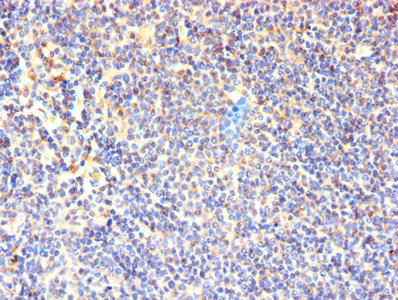

圖片:

應用范圍:ELISA, IHC

Application Recommended Dilution IHC 1:20-1:200 -